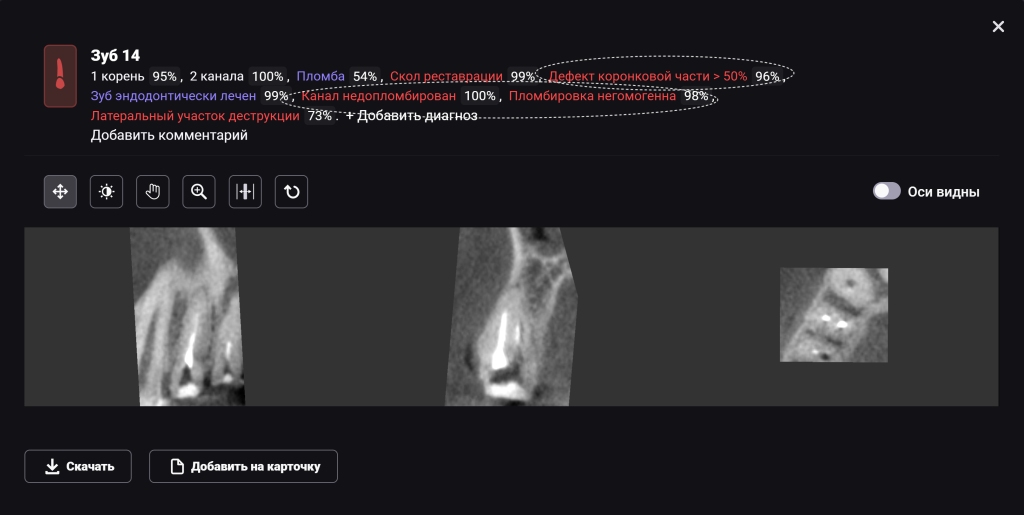

Для принятия клинического решения врач проанализировал данные осмотра и рентгенологического отчета Diagnocat. В отчете содержится оценка ранее проведенного лечения и данные о наличие признаков периапикальных изменений

Обратите внимание на высокий процент вероятности, который предлагает Diagnocat. Принято решение о сохранении зубов и проведении повторного эндодонтического лечения